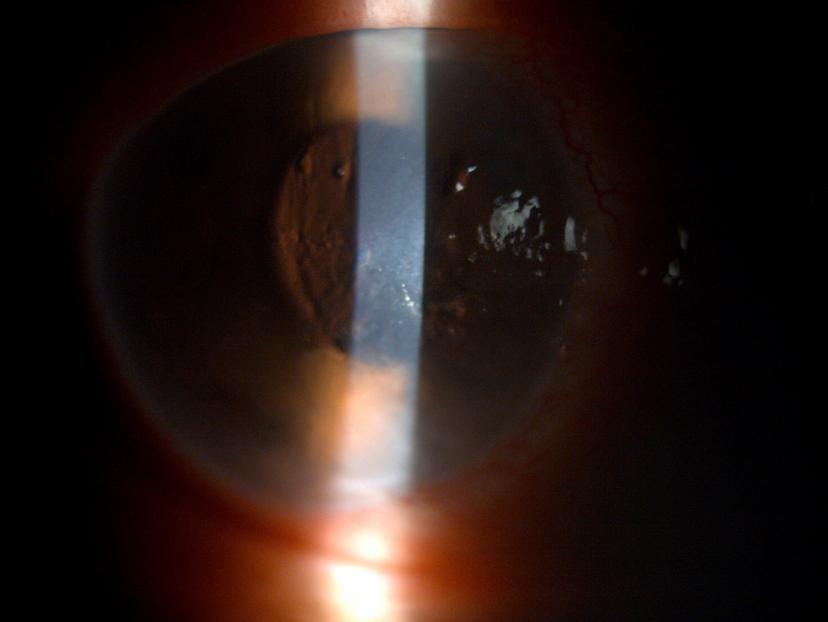

前房水蛋白增加会产生闪辉的光学现象(见图1),房

这张眼科图像描绘了房水流入眼睛的前房,并通过房周周围的小梁网流出.